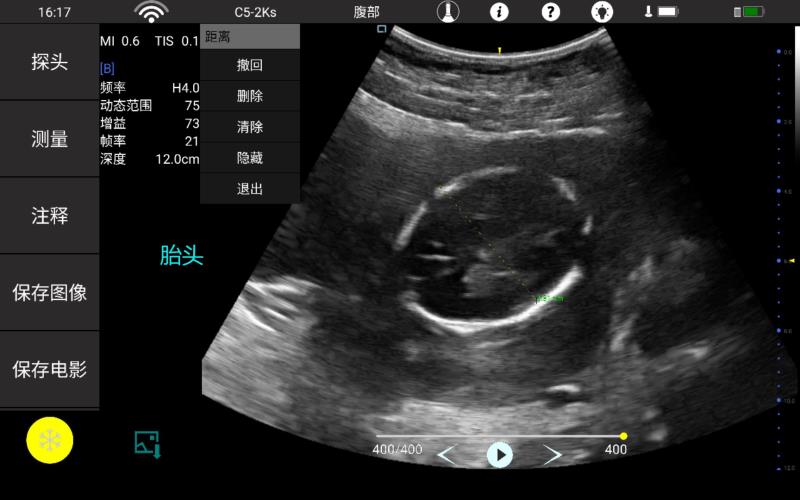

• 大凸

腹部

肾脏

妇科产科

心脏

肺等